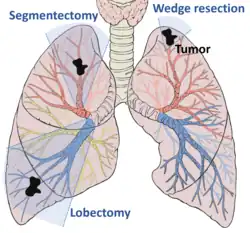

For stage I and stage II NSCLC the first line of treatment is often surgical removal of the affected lobe of the lung.[44] For those not well enough to tolerate full lobe removal, a smaller chunk of lung tissue can be removed by wedge resection or segmentectomy surgery.[44] Those with centrally located tumors and otherwise-healthy respiratory systems may have more extreme surgery to remove an entire lung (pneumonectomy).[44] Experienced thoracic surgeons, and a high-volume surgery clinic improve chances of survival.[44] Those who are unable or unwilling to undergo surgery can instead receive radiation therapy. Stereotactic body radiation therapy is best practice, typically administered several times over 1–2 weeks.[44] Chemotherapy has little effect in those with stage I NSCLC, and may worsen disease outcomes in those with the earliest disease. In those with stage II disease, chemotherapy is usually initiated six to twelve weeks after surgery, with up to four cycles of cisplatin – or carboplatin in those with kidney problems, neuropathy, or hearing impairment – combined with vinorelbine, pemetrexed, gemcitabine, or docetaxel.[44]

The first successful pneumonectomy for lung cancer was performed in 1933 by Evarts Graham at Barnes Hospital in St. Louis, Missouri.[115] Over the following decades, surgical development focused on sparing as much healthy lung tissue as possible, with the lobectomy surpassing the pneumectomy in frequency by the 1960s, and the wedge resection appearing in the early 1970s.[116][117] This trend continued with the development of video-assisted thoracoscopic surgery in the 1980s, now widely performed for many lung cancer surgeries.[118]